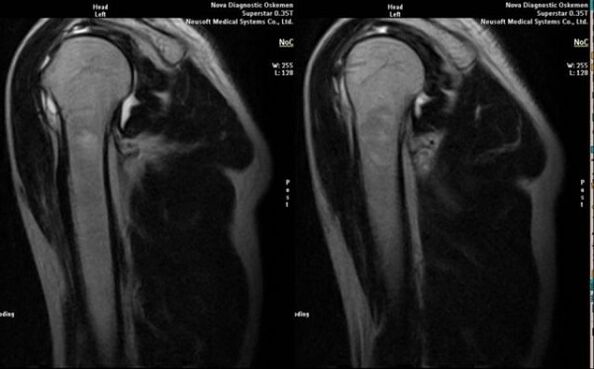

- magnetska rezonancija i kompjutorizirana tomografija;

Znakovi koji izravno upućuju na razvoj artroze uključuju pojavu značajnog suženja zglobne šupljine, sklerozu subkartilaginoznih struktura, stanjivanje samog sloja hondrocita, pojavu osteofita i taloženje kristala soli u intraartikularnoj tekućini.